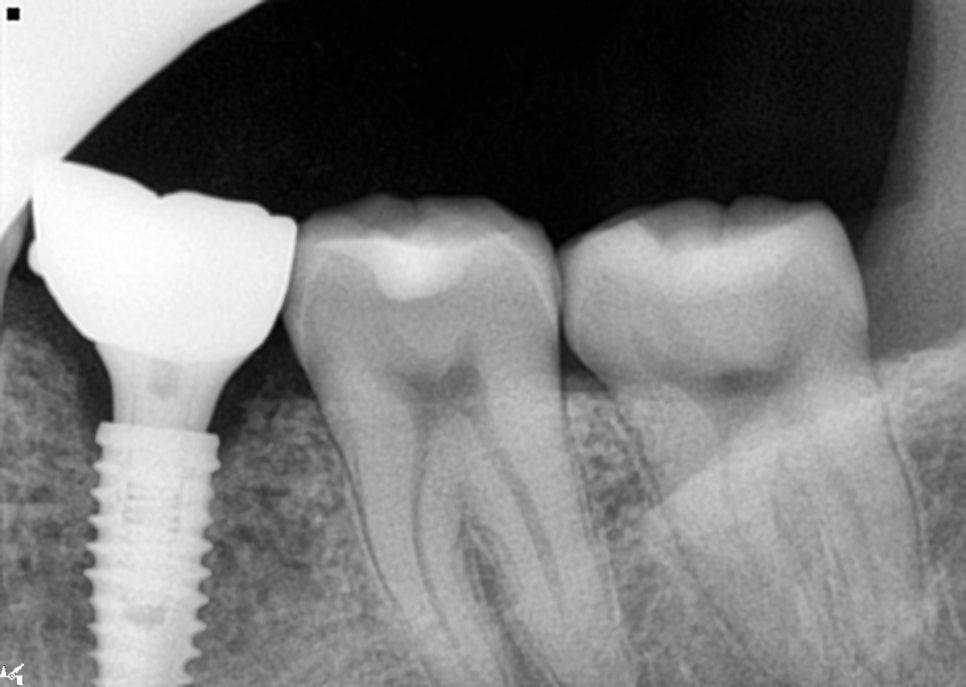

최종보철 수복 및 완료

드디어 이 긴 치료의 마지막 단계

최종 크라운을 제작하고

장착을 하는 과정인데요.

이 단계에서는 여러가지를 체크를 해야합니다.

최종보철시 위 아래의 치아가 편안하게

맞물리게 되었는지

옆 치아와 자연스럽게 닿는지

색상과 형태가 자연스러운지

방사선으로 최종확인까지 해야합니다.

특히나 교합조정은 정말 세밀하게

진행을 해야하거든요.

아래쪽 보철 완

너무 높으면 맞닿을 때 불편할 수 있고

너무 낮으면 제대로 된 기능을

못할 수 있기 때문에 미세한 조정은

불가피한 부분이에요.

최종완성 4개 부위 임플란트 모두 성공적으로 마무리

인접한 치아와의 접촉점도

너무 꽉 끼거나 헐거우면 절대 안되고요.